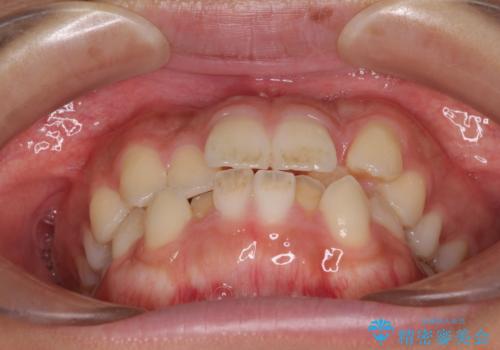

- 前歯のデコボコと口元の突出感を気にして来院された患者様です。

上下左右第一小臼歯4本を抜歯し、ワイヤー装置にて口元を引っ込めるよう矯正治療を行うこととしました。